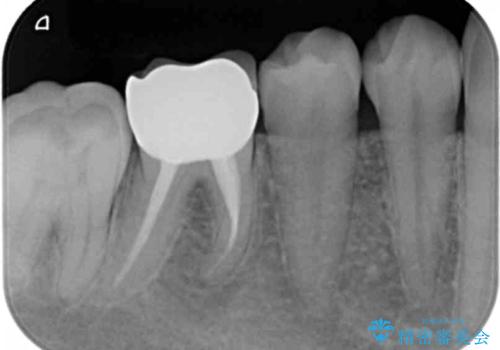

- 右下の奥歯に入れた銀歯を白くしたいとのことで来院されました。

根っこの治療がされていますが、症状もなくレントゲン画像で病変も確認できないため根管内には触れず被せ物のやり替えのみとなりました。